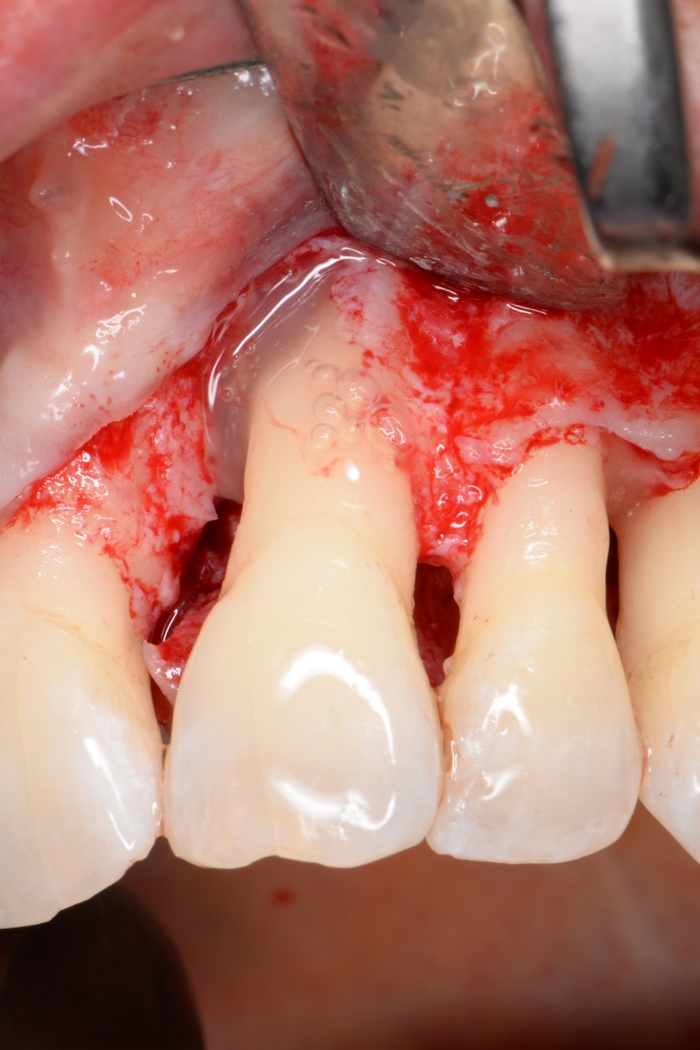

Herr Dr. Tunkel, die Regeneration parodontaler Strukturen ist das Hauptziel einer jeden Parodontalbehandlung. Welche Maßnahmen stehen Zahnärzten heute zur Verfügung? Dem Zahnarzt stehen prinzipiell die Verwendung von Membranen, welche heutzutage meist resorbierbar sind, sowie Schmelz-Matrix-Proteinen, z. B. Emdogain (Straumann), zur Verfügung. Dies kann man noch mit verschiedenen autologen, allogenen, xenogenen oder synthetischen Knochenfüllern kombinieren. Die Kombination von Membran und Schmelz-Matrix-Proteinen macht nach derzeitigem Stand der Wissenschaft keinen Sinn.

Inwiefern hängt der Erfolg einer regenerativen Therapie von den verwendeten Materialien ab? Der Erfolg der regenerativen Maßnahme hängt in erster Linie von der Einbettung in ein erfolgreiches parodontales Gesamtkonzept ab. Dies beginnt mit der antiinfektiösen Therapie, läuft weiter in einer sauber durchgeführten regenerativen Maßnahme und endet in einer guten postoperativen und langfristigen Nachsorge. Die Verwendung verschiedener Materialien bedingt nicht in erster Linie den Erfolg, sondern ermöglicht es, die Eingriffe weniger invasiv und effizienter zu machen.

Welchen Einfluss hat das bakterielle Gleichgewicht im Mund auf die Behandlung? Einen großen Einfluss. Sowohl die antiinfektiöse Therapie, um das bakterielle Gleichgewicht nachhaltig zum Positiven zu verändern, die direkt präoperativ durchgeführt antimikrobielle Behandlung, um die Bakterienzahl vor dem parodontalen Eingriff zu minimieren, als auch die postoperative Infektionskontrolle haben einen deutlich positiven Effekt auf das Ergebnis der Regeneration.